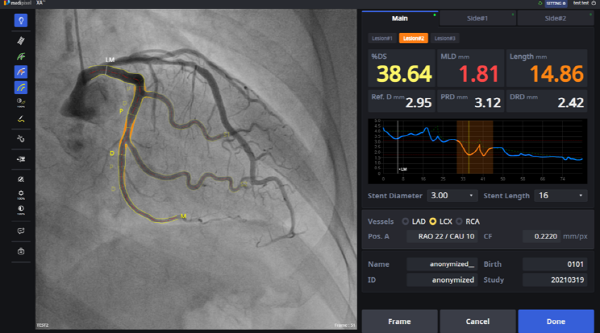

▲ 메디픽셀 특허 기술이 적용된 AI 솔루션 ‘Medipixel XA’’

이 기술은 인공지능(AI)으로 정교하게 훈련된 알고리즘이 관상동맥 혈관을 분할(segmentation)해주는 방법으로 1~2초 만에 혈관을 추출한 뒤 병변을 분석해 정량화하는 과정의 핵심기술이다.

메디픽셀이 FDA 승인을 받은 제품도 이 특허 기술을 기반으로 했다. 기존 외국 경쟁 제품들은 추가 수작업이 필요해 분석 시간이 길고 정확도가 떨어져 시술실에서 사용되지 못하는 반면, 메디픽셀 솔루션은 독자 기술을 바탕으로 제품의 완전 자동화를 구현해 실시간 사용이 가능하도록 한 점이 특징이다. 업계에서 기존의 심혈관 중재 시술의 진단과 치료 방법에서 혁신을 선도하고 있다는 평가를 받고 있다.